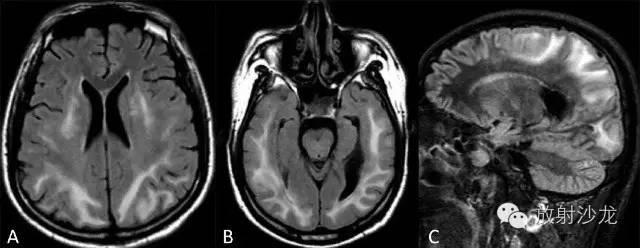

双侧幕上半球放射冠区多发斑片状异常信号区。T1WI(A)为稍低信号,T2WI(B)为高信号,FLAIR(C)呈不均匀稍高信号,占位效应不明显。

肿块样的ms,但较之肿瘤水肿轻,和对白质压迫的作用。